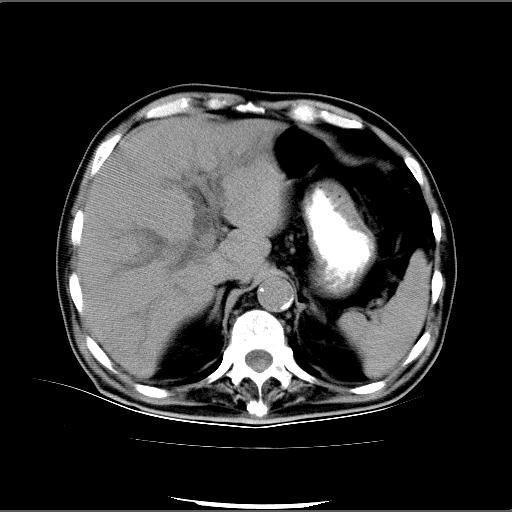

患者男82岁,黄染,发热10天,无腹痛。

1胆总管下端结石伴肝内外胆管扩张;2胆囊颈部结石伴胆囊积液

胆囊多发结石,胆囊积液;胆总管中下段结石,中上段扩张。

胆总管下段结石伴胆道系统扩张;胆囊炎伴胆囊结石.

1、胆总管壶腹部结石并胆总管、胆囊及肝内胆管扩张。2、胆囊多发结石。3、两下胸膜局限性增厚。4、胃体部大弯侧胃壁稍厚,建议:多量饮水后增强ct扫描除外占位性病变。

此病例有结果了:患者术后为:胆总管下段结石伴胆道系统扩张;胆囊炎伴胆囊结石。

各位战友分析的都很正确,是一个典型的病例。